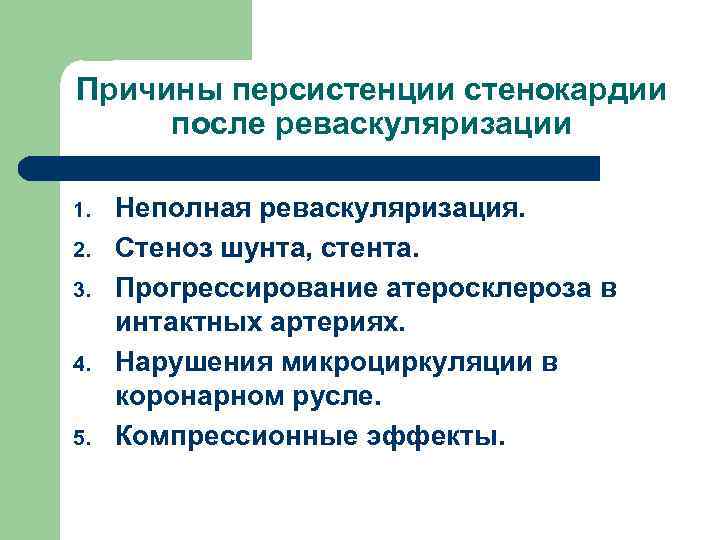

Причины персистенции стенокардии после реваскуляризации 1. 2. 3. 4. 5. Неполная реваскуляризация. Стеноз шунта, стента. Прогрессирование атеросклероза в интактных артериях. Нарушения микроциркуляции в коронарном русле. Компрессионные эффекты.